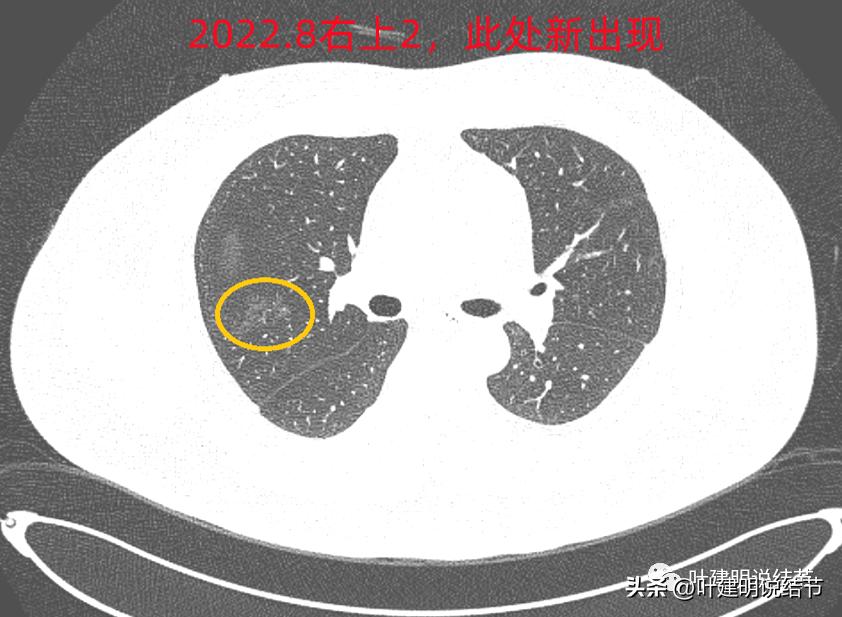

右上叶倒又出现了新的病灶:

右上病灶2:新出现的,整体轮廓较清,但感觉较散在,不致密,也不是圆形或类圆形,大概是炎性的吧!

2020年时同样位置是没有异常的:

还敢判定右上的病灶是恶性范围的不典型增生或原位癌吗?我是连左上病灶4都不敢了!还好,我觉得我们不必去纠结这几个病灶到底是不是肺癌或腺体前驱病变,反正至少风险很低,能随访就是了,肯定不能建议手术或消融等干预,也不需要穿刺活检。只要仍继续随访,半年吧!将结果交给时间来判断。